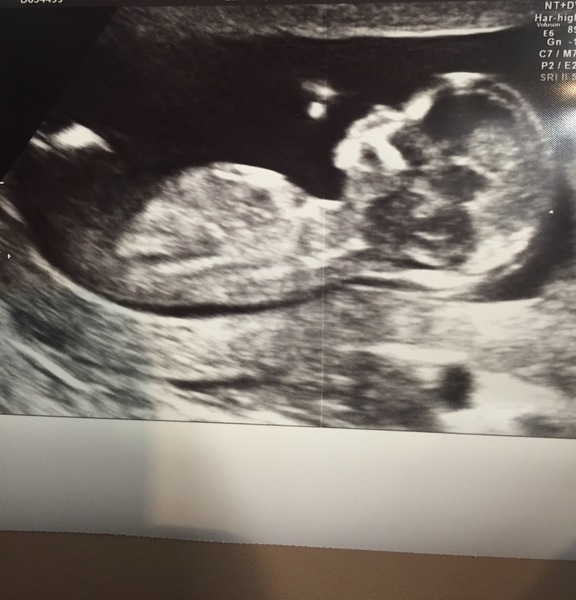

Hugs and good luck for scans today